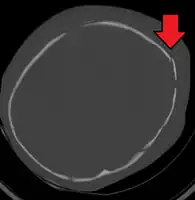

AHT may be misdiagnosed, underdiagnosed, and overdiagnosed,[26] and caregivers may lie or be unaware of the mechanism of injury.[11] Commonly, there are no externally visible signs of the condition.[11] Examination by an experienced ophthalmologist is often critical in diagnosing shaken baby syndrome, as particular forms of ocular bleeding are quite characteristic.[27] Magnetic resonance imaging may also depict retinal bleeding;[28] this may occasionally be useful if an ophthalmologist examination is delayed or unavailable. Conditions that are often excluded by clinicians include hydrocephalus, sudden infant death syndrome (SIDS), seizure disorders, and infectious or congenital diseases like meningitis and metabolic disorders.[29][30] CT scanning and magnetic resonance imaging are used to diagnose the condition.[11] Conditions that may accompany AHT include bone fractures, injury to the cervical spine (in the neck), retinal bleeding, cerebral bleed or atrophy, hydrocephalus, and papilledema (swelling of the optic disc).[12]